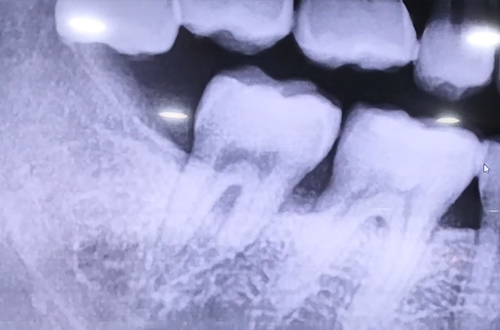

잇몸치료 및 즉시 임플란트 사례

치료 유형 어금니 즉시 임플란트

오른쪽 큰 어금니의 붓기로 내원해 주신 분으로,

겉으로는 보이지 않는 잇몸 안쪽의 염증이 발견되신 사례입니다.

본 사례의 경우 잇몸 치료와 함께 문제가 발생한 부분의 어금니를 발치한 후

즉시 임플란트를 진행하였고, 그 주변의 자연치아 어금니의 잇몸도

상태가 나빠지지 않도록 지속적인 관리에 힘쓸 것입니다.